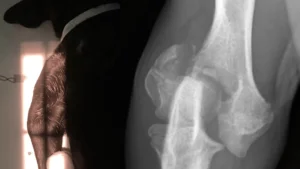

X-Ray / Ultrasound

We are pleased to accept outpatient referrals for X-Ray and Ultrasound.